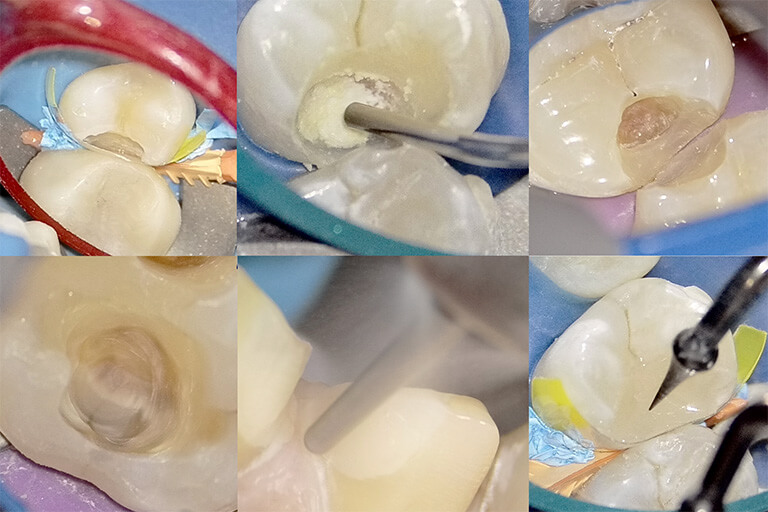

必須条件1:ラバーダム防湿

私たちの口の中には、常に唾液が存在します。この唾液1滴の中には、数億個もの細菌が含まれています。もし治療中に、この唾液がほんの少しでも削った面に付着すればどうなるでしょうか?

- 細菌を歯の中に閉じ込めたまま蓋をしてしまい、内部で虫歯が再発する。

- コーティング剤や接着剤の接着力が、湿気によって著しく低下し、すぐに剥がれたり隙間ができたりする。

このような事態を防ぎ、完璧な清潔・乾燥状態を作り出すために絶対に必要なのが「ラバーダム防湿」です。これは、治療する歯だけをゴムのシートから隔離する処置です。 これを行うことで、治療部位を唾液や呼気に含まれる湿気から完全にシャットアウトできます。日本ではまだ導入率が低いのが現状ですが、再発を防ぐ治療においては、もはや「常識」であり「必須」の処置です。

必須条件2:歯科用顕微鏡(マイクロスコープ)

コーティング法は、ミクロン単位の精度が要求される、非常に繊細な治療です。肉眼では、どれだけ優れた歯科医師でも、経験と勘に頼らざるを得ない部分が出てきます。

しかし、歯科用顕微鏡(マイクロスコープ)を使えば、視野を最大で20倍以上にまで拡大できます。これにより、

- 虫歯の取り残しを確実に防ぐ

- 肉眼では見つけられないようなむし歯をしっかりと取り除くことができる

- 健康な歯を削りすぎることを防ぐ

- 肉眼では見えない微細な亀裂や段差を見つけ出す

- コーティング剤を、本当に隙間なく歯の表面に塗り広げられているかを確認する

といったことが可能になります。マイクロスコープを使用しないと、完璧なコーティングは難しいでしょう。成功することもあるかもしれませんが、その確実性は著しく低くなってしまうでしょう。

当院、NK dental TOKYOでの虫歯の再発率が非常に低いのも、虫歯治療において、この「ラバーダム防湿」と「マイクロスコープ」を用いた精密なコーティング法を徹底しているからに他なりません。